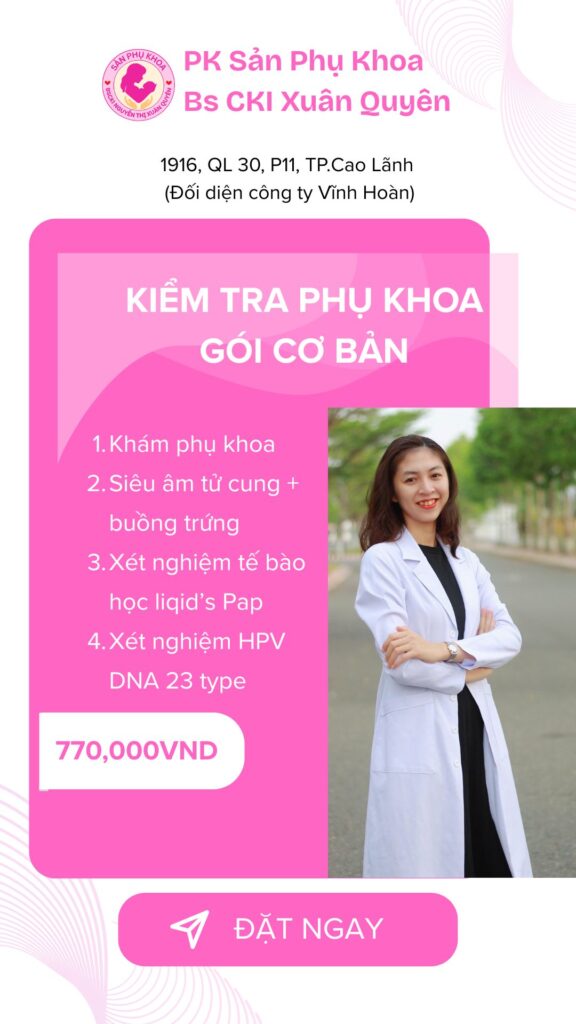

Bảng Giá tham khảo

Gói dịch vụ

gói kiểm tra phụ khoa cơ bản